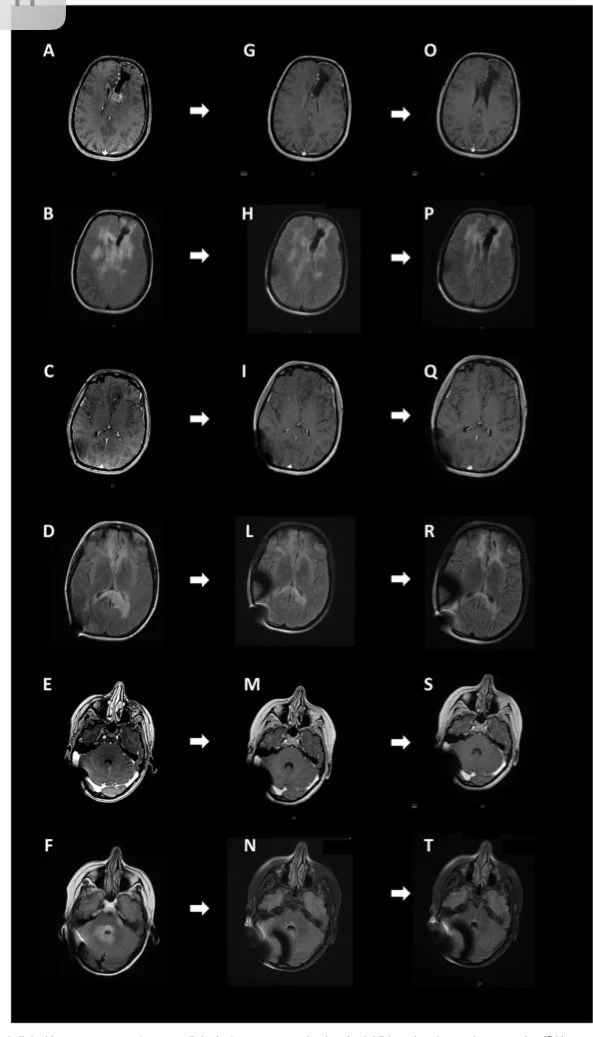

Title: Advances in the management of patients with IDH-mutant glioma